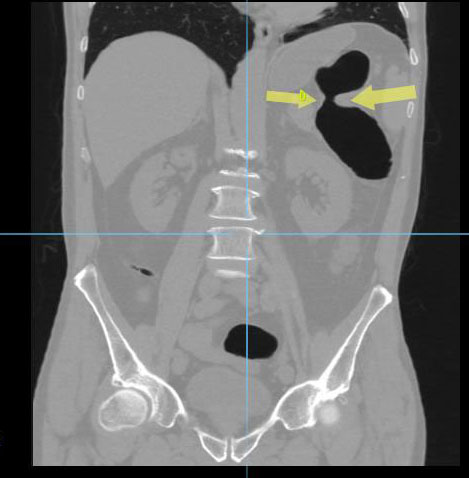

Циркулярный рак тонкой (подвздошной кишки)

Необходимо отметить, что данная патология довольно редко встречается, как правило выявляется на операционном столе у пациентов с тонкокишечной непроходимостью. На данном примере демонстрируем, что дефект кишки был диагностирован на основании 3D реконструкции, а затем уже целенаправленно подтвержден сканограммами с протяженностью процесса и степенью сужения кишечной трубки. Сыграла свою роль сопутствующая патология, которая имела место быть, а именно слабость Баугиниевой заслонки, за счёт чего тонкий кишечник полностью заполнился газом, хотя целью исследования было исключить патологию толстого кишечника.